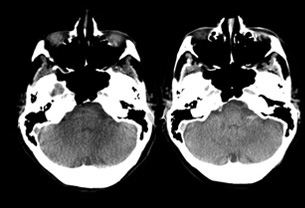

Der Arbeitsablauf der Direct to Angio Suite bietet wertvolle und zeitsparende Unterstützung bei verlegten oder neuen Patienten, die im spezialisierten Schlaganfall-Zentrum eintreffen. Die Zeit bis zur Reperfusion ist das entscheidende Kriterium zur Verringerung von Morbidität und Mortalität bei akuten Schlaganfällen.4,5

Bei Patienten, die sich direkt in einem für endovaskuläre Behandlungen ausgestatteten Zentrum vorstellen, liegt der Fokus primär auf der Verkürzung der Zeit vom Eintreffen des Patienten bis zur Bildgebung und der Zeit von der Bildgebung bis zum Leistenzugang. Patienten, die zunächst eine externe Einrichtung aufsuchen, sind mit weiteren Verzögerungsfaktoren wie einem längeren Aufenthalt bis zum Abtransport aus der Erstversorgungseinrichtung, längeren Transportzeiten und zusätzlichen Untersuchungen im endovaskulären Behandlungszentrum konfrontiert.6

Die Arbeitsabläufe der Direct to Angio Suite ermöglichen die Durchführung einer umfassenden Schlaganfalldiagnose direkt in der Neuro Angio Suite – eine wertvolle und zeitsparende Unterstützung für Patienten in kritischem Zustand, die auf eine schnelle mechanische Thrombektomie-Therapie angewiesen sind.